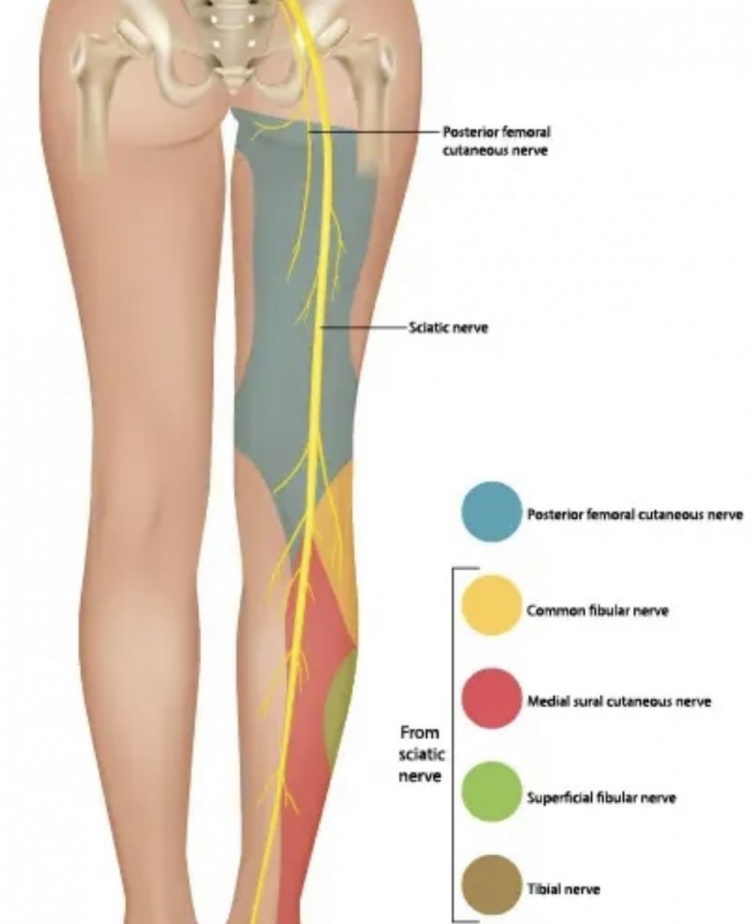

这一术语来源于坐骨神经,它从脊柱发出,沿着腿向下延伸,并在途中分出许多分支。

就勒布朗而言,在球队声明他患有坐骨神经痛之前,据说他正在应对“臀部神经刺激”的问题,这指的是构成髋部和下背部的臀肌。这些肌肉由多条神经支配。

基于以上信息,我们知道勒布朗可能正在应对高位神经刺激问题。如果他确实遭受的是坐骨神经痛,而不是一个笼统的诊断,这或许是一个积极信号,因为通常情况下,坐骨神经痛越严重,疼痛感会越往腿部下方延伸(远端),而不是集中在背部区域(近端)。